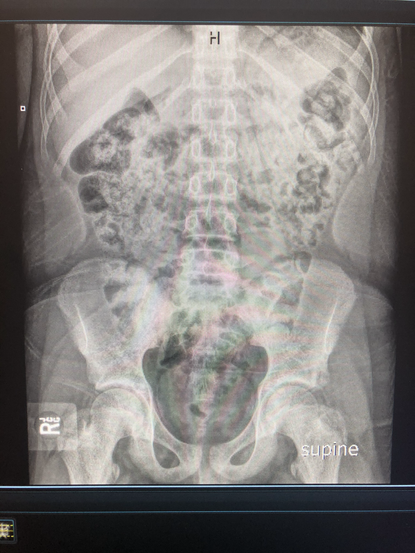

These xrays are a drop in the bucket. So much gas. So much poop. Every single person complaining of abdominal pain with no idea (?!) why they are hurting. Every single person complaining of cramping, sharp pains, no appetite, nausea, sometimes vomiting. Also, a topic for another day, is that people somehow almost never relate what they EAT, to how their STOMACHS feel! Guys - food is medicine or poison - it will catch up with you in one way or another. Eating poorly doesn't always mean a heart attack or a stroke, or obesity or high cholesterol. The big bad warnings on public service announcements and commercials aren't the only consequences of a bad diet, lack of water and lack of exercise/activity. Living on boxed, frozen, fast, fried, greasy foods with little to no fruits, vegetables and water is absolutely going to catch up with you.